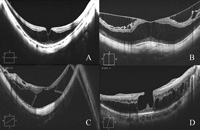

7 para explicar el aspecto biomicroscópico de desprendimiento de retina en algunos pacientes con alta miopía. La OCT de dominio espectral ha permitido el estudio detallado del segmento posterior, y ha ayudado a resolver ciertos casos de pérdida de agudeza visual en pacientes con alta miopía sin cambios evidentes en el fondo de ojo (

Figura 2).

Figura 2. Diferentes aspectos tomográficos en pacientes con retinosquisis miópica. A) Foveosquisis externa sin signos de tracción vitreomacular visibles. B) Foveosquisis interna y externa. C) Foveosquisis con desprendimiento foveal y agujero lamelar externo. D) Foveosquisis externa con agujero lamelar interno y restos del córtex vítreo adheridos a la superficie interna de la retina.